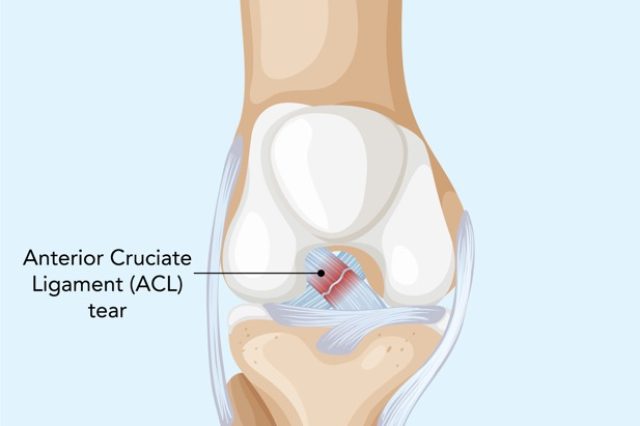

ACL Ligament Treatment

Advanced ACL ligament treatment with arthroscopic surgery, ligament reconstruction, and physiotherapy for stable knee movement and faster recovery.